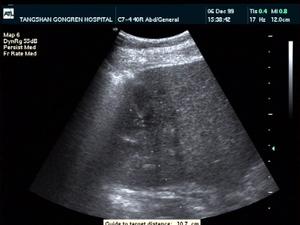

2.超音波檢查可發現膿腫部位有典型的液性回聲暗區或膿腫內液平面。該檢查除能協助臨床診斷外,還可以幫助了解膿腔的部位、大小及距體表的深度,以便確定膿腫的最佳穿刺點和進針方向與深度,或為手術引流提供入路選擇。但超聲對小於1cm的多發性肝膿腫,往往難以發現,臨床診斷時應予注意。從超聲學的角度,還需要與其他囊性病變鑑別。一般情況下,肝囊腫的囊壁整齊清晰,囊內密度均勻一致。而肝膿腫的腔壁不規則,界限不清楚,腔內常含有多個回聲區。